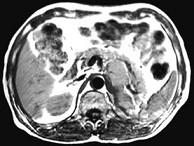

问题 女,34岁,无意中发现血压升高4个月就诊,行CT检查,如图所示,下列说法正确的是()

选项 A.CT示左侧肾上腺区可见一等密度块影,边界清楚 B.增强扫描,该病灶周边明显强化,中心处强化不明显 C.考虑为左肾上腺腺瘤 D.考虑为左肾上腺嗜铬细胞瘤 E.考虑为左肾上腺转移瘤

答案 ABD